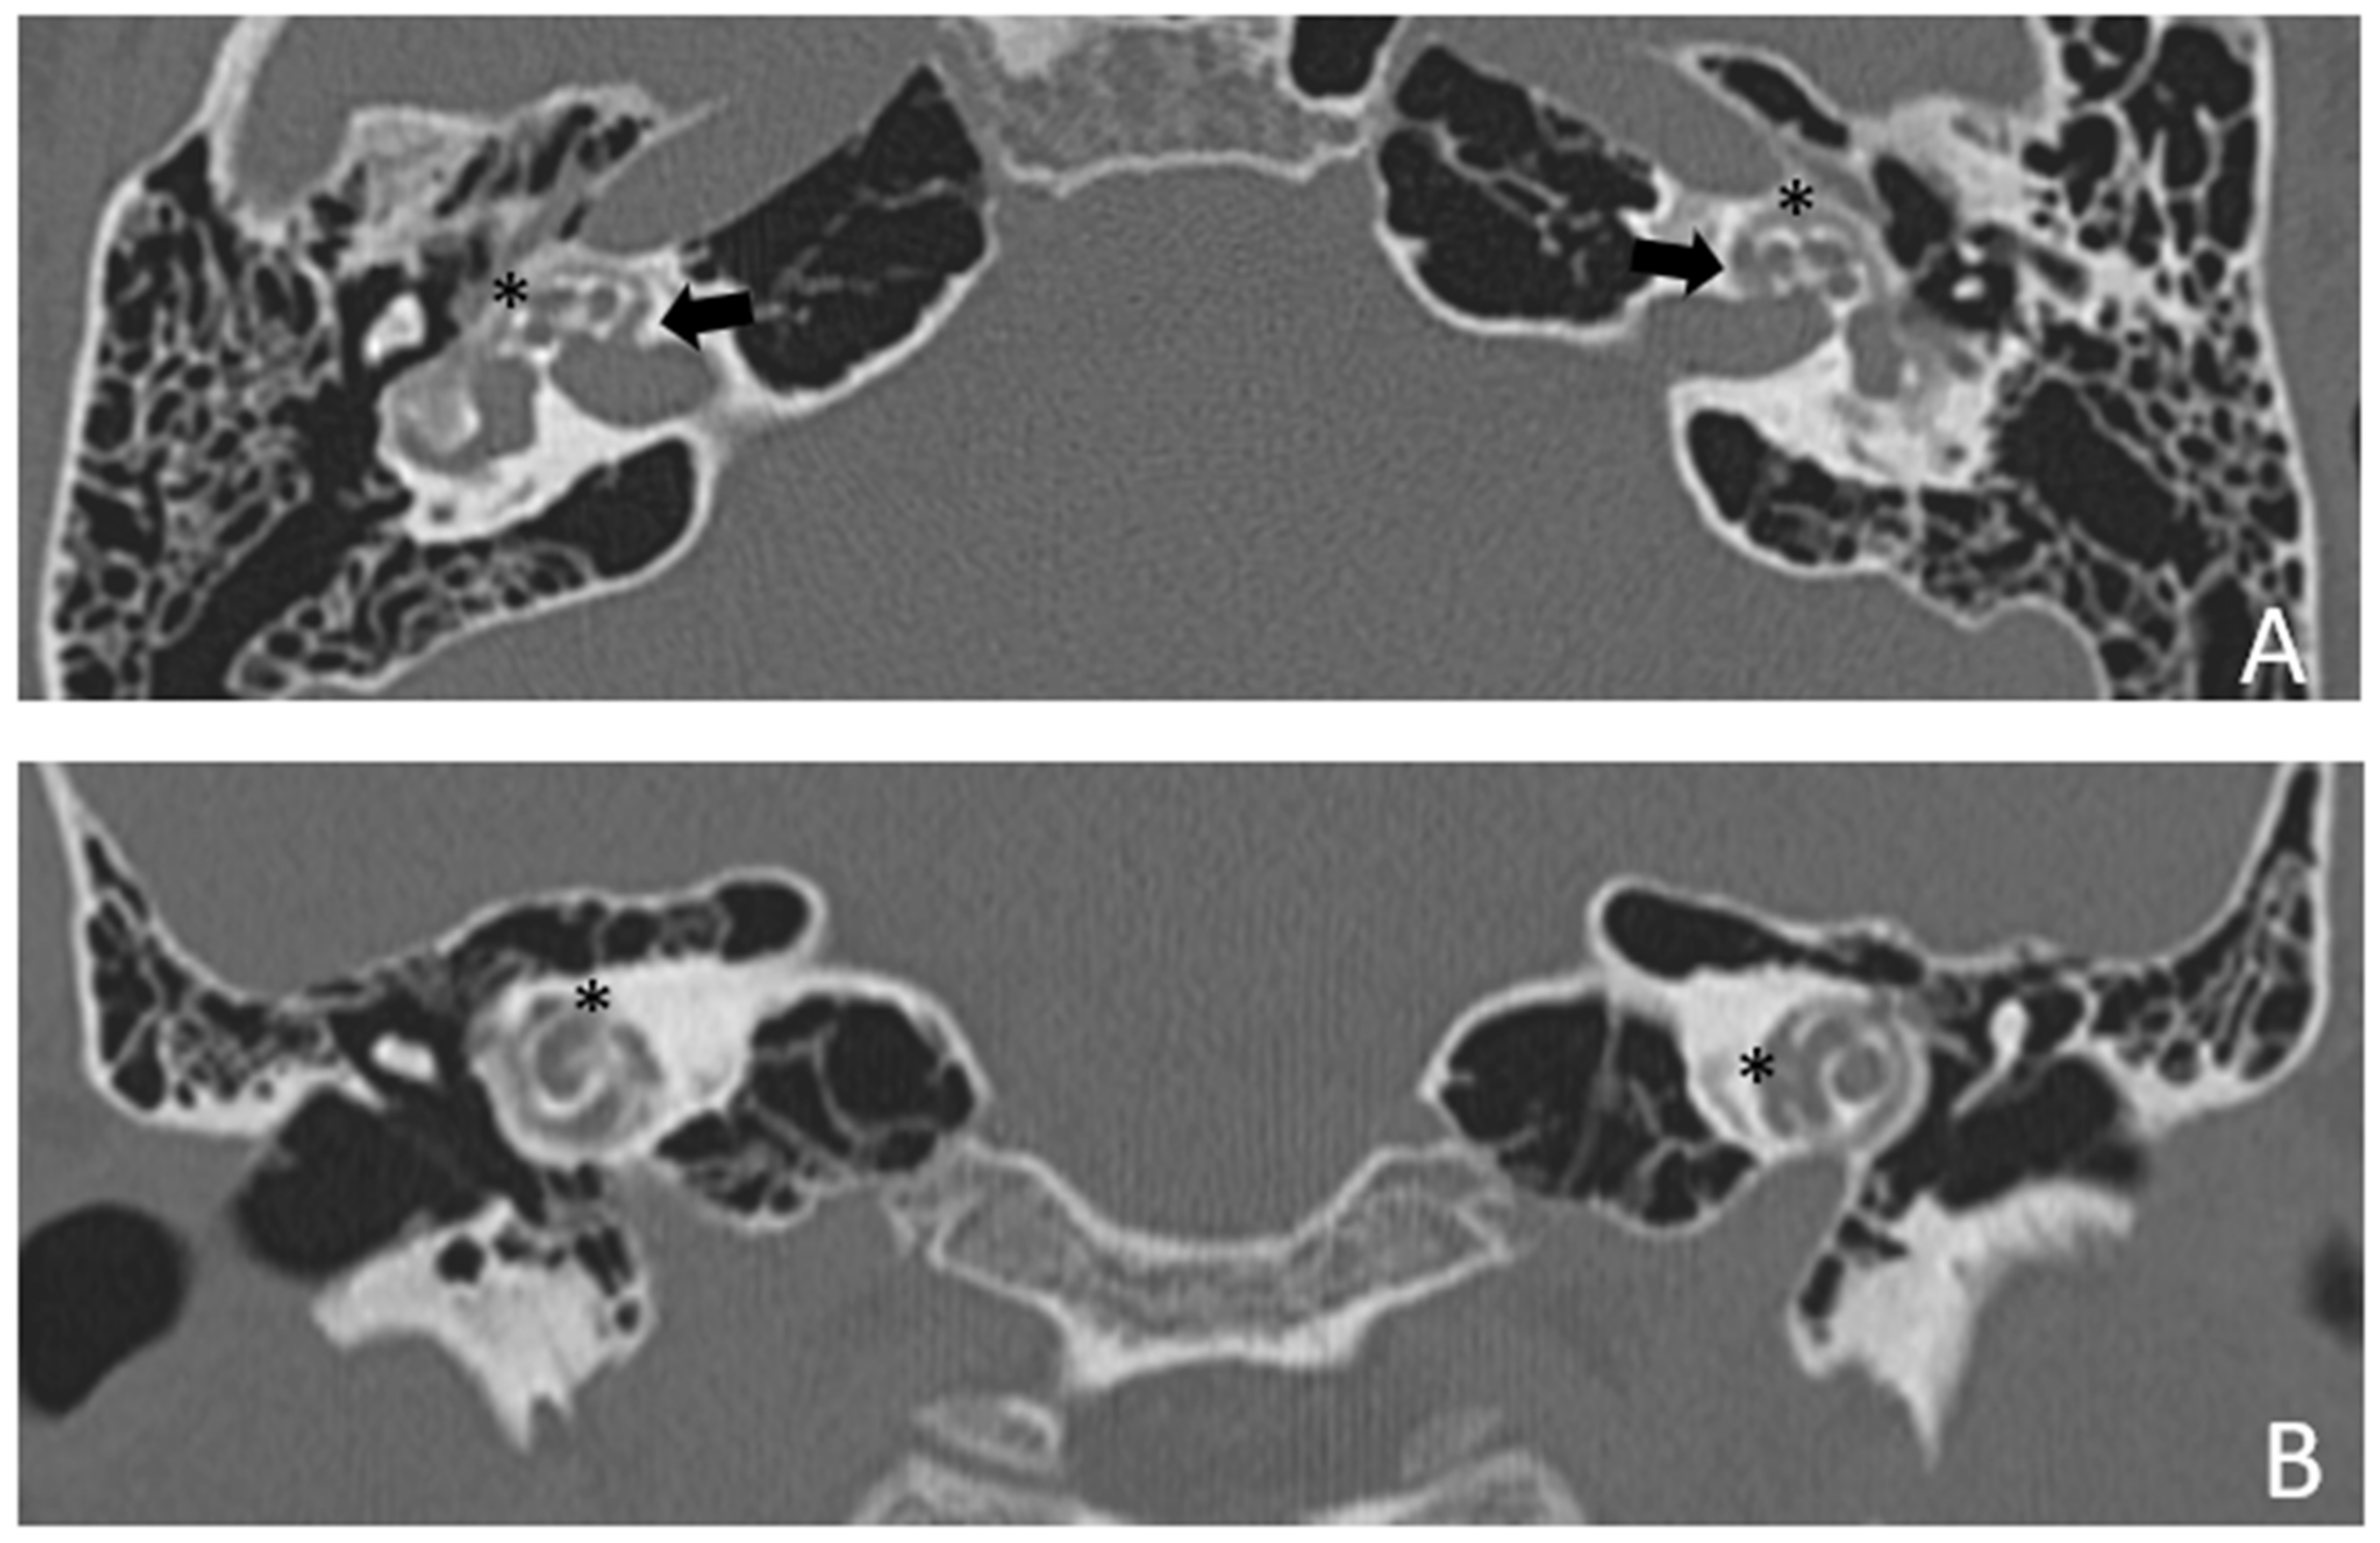

Figure 3.

CT images of patient #2 with osteogenesis imperfecta. (A), axial plane; (B), coronal plane. A large pericochlear cavity is visible; arrows indicate its origin from the IAC, asterisks indicate the communication of the cavities with the cochlea.

Patient #2, affected by OI-type I (COL1A1 mutation). MHL since diagnosis. Bone threshold was similar in both ears, but PTA was worse in the right ear with a larger ABG. HL progressed, but the difference between the two sides was maintained. The patient was fitted with conventional hearing aids bilaterally. Stapes surgery was not performed because of the radiological aspect (Figure 3 and Figure 4): a large cavity is present bilaterally and diffused communication between the cavity and the cochlea is evident.